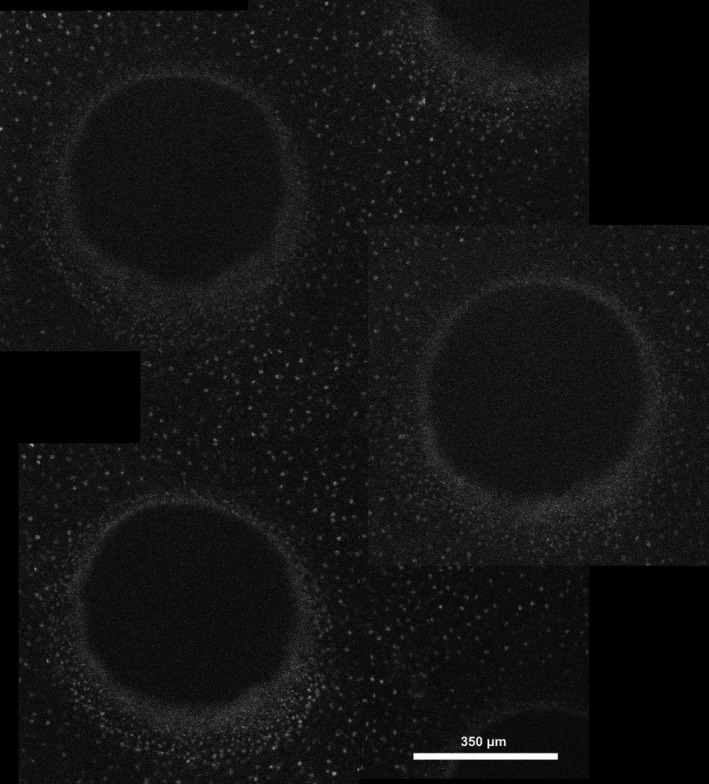

All 220 corneas were de‐epithelialized, either manually (n = 88) or excimer laser‐assisted (n = 132). Full manual de‐epithelialization of the central epithelium with a 9 mm diameter was performed using a blunt hockey knife, following the Dresden protocol (Wollensak, Spoerl & Seiler 2003), similar to clinical practice without the application of alcohol. Selective patterned de‐epithelialization was performed over the central 9 mm using the SCHWIND Amaris excimer laser (SCHWIND Eye‐Tech‐Solutions, Kleinostheim, Germany). Epithelial channels with a radius of 350 μm, the minimal radius possible for this excimer laser apparatus, were created in a hexagonal pattern with equal distance between channels (Fig. 1, Fig. 2, supplementary Figure S1). Pilot studies showed chromophore diffusion became heterogenous if the spacing between channels was greater than 375 μm. Thus, the distance between channels was set at 375 μm, resulting in approximately 40% total surface ablation of the treated area (Supplementary equation S1). Ablation depth was determined for each cornea individually and set to penetrate the full epithelial thickness, measured by ocular coherence tomography (OCT), as described below.

Fig. 2.

Stitched image derived by fluorescence microscopy showing several epithelial channels, and intermediate remaining epithelium, with cell nuclei stained by propidium iodine.

Confocal fluorescence microscopy

After absorbance spectrophotometry, corneal chromophore diffusion was assessed using an inverted confocal fluorescence microscope (BX61 Olympus, Tokyo, Japan), with images taken at 10 µm steps using a CCD camera (Cascade 512B, Roper Sci., New Jersey, USA). Samples were stained by 5 µM propidium iodine (PI), allowing visualization of the sample’s stromal borders. All samples were excited at 561 nm with fluorescence being recorded at 617 nm to image PI‐stained cell nuclei. Additionally, samples were consecutively excited at 488 nm (RF‐based impregnated corneas) or 755 nm (WST11‐based impregnated corneas), or at both 488 nm and 755 nm (unimpregnated control corneas). Fluorescence intensity was recorded above 525 nm and 760 nm using a filter, for RF and WST respectively. Per cornea, above‐mentioned images were taken at three (mechanically de‐epithelialized samples) or six (excimer laser‐assisted de‐epithelialized samples) different areas. In the latter, three areas each were taken, manually centred at either an epithelial channel or a non‐ablated area (Fig. 1). Samples were measured from endothelium to epithelium, to avoid the influence of photobleaching and clear imaging of the chromophore’s penetration front depth. Per image, the intensity in the central 100x100 pixels for both measured channels was averaged and plotted against the depth into the sample, using MATLAB (MATLAB R2018b; The MathWorks Inc., Natick, USA). The stromal border’s position, visualized by the PI staining, was used to determine each frame’s depth within that specific corneal sample. Intensity plots corresponding to RF and WST11 were baseline corrected. Penetration depth was determined to be the point where the intensity dropped below a predetermined threshold value of 30 A.U., below which the signal was considered noise. Supplemental Figure S2 shows a representative example of the output generated by above‐mentioned method of a RF impregnated cornea after excimer laser ablation. Per cornea in the excimer laser‐assisted group six such graphs were generated (following the sampled areas as shown in figure 1), with three areas sampled in the manual de‐epithelialization group.